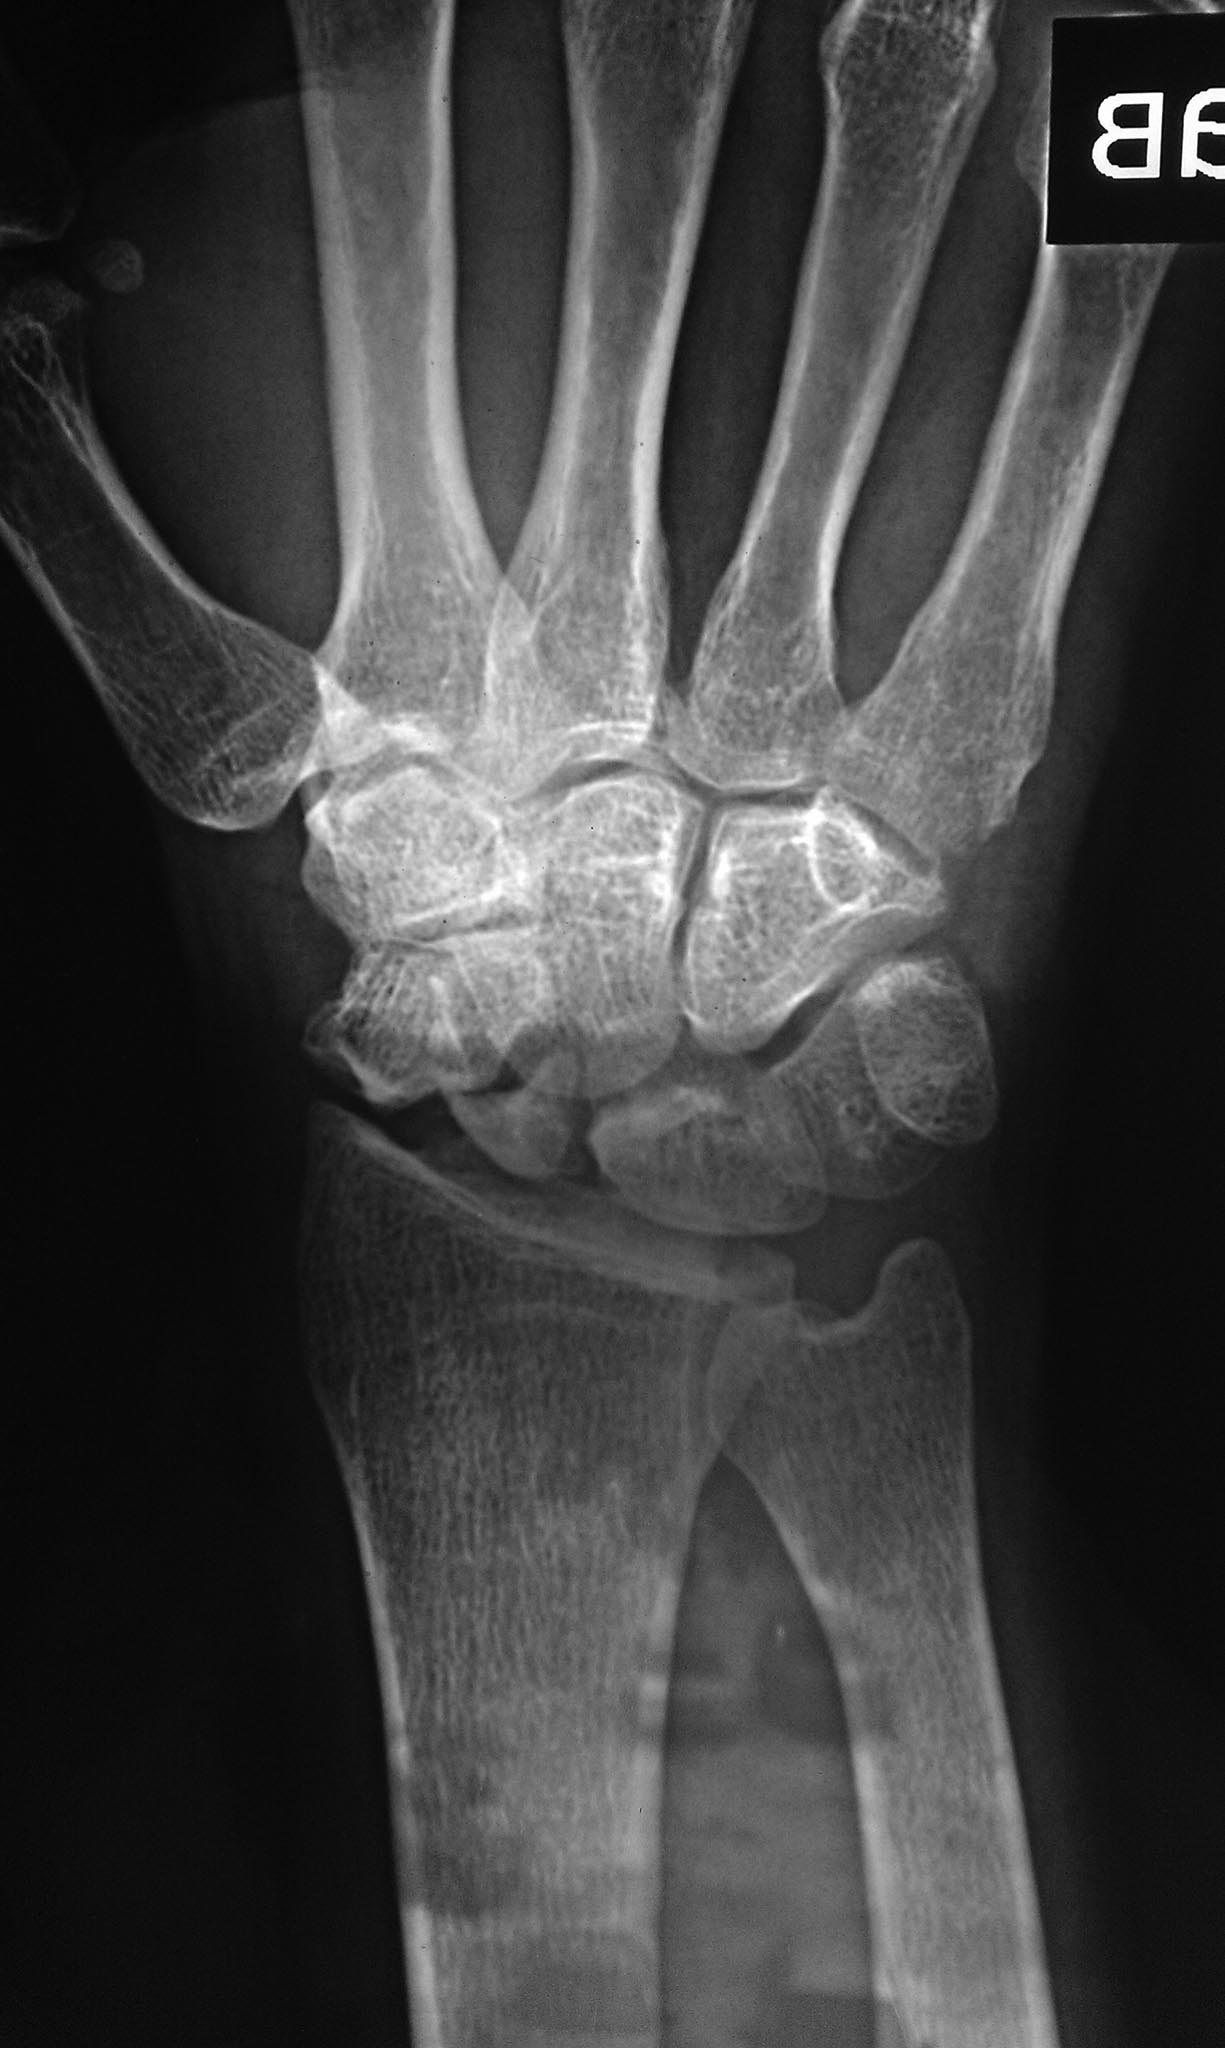

Свежего перелома не вижу. Есть несросшийся перелом ладьевидной кости. Также артроз л/зап. сустава уже есть, видимо травма старинная.

перелом явно старый, более 1 года. Сформировался ложный сустав, есть признаки артроза. Учитывая молодой возраст, возможно стоит рассмотреть остеосинтез винтами Герберта с костной аутопластикой. Надо зачистить шип на ладье, возможно удалить верхушку шиловидного отростка лучевой кости. Еще- в плане личного восприятия- снимки и репозиция все-таки делаются В АППАРАТЕ, а не НА.

Ложный сустав ладьевидной кости не вызывает сомнений, причём до 4.02.2016 - без клинической манифестации. 4.02.2016-травма и подвывих на уровне ложного сустава.

Ну о каком свежем переломе может идти речь??? Этому перелому уже 3-4-5 лет!!!! Сделайте компьютерную томографию и Вы поймете однозначно, что как проксимальный так и дистальный фрагменты нежизнеспособны и полны кист и никакая костная пластика их не спасет!!! Так же имеется грубые изменения в самом суставе!!! Диагноз - деформирующий артроз кистевого сустава III cт. на фоне псевдоартроза ладьевидной кости с фрагментацией и асептическим некрозом фрагментов ладьевидной кости SNAC (Scaphoid Nonunion Advanced Collapse). В данном случае есть 2 пути - 1 - провести консервативную терапию - гипсовую лонгету, НПВП, физ. методы и аппараты внешней фиксации здесь абсолютно не нужен!!! и беречь эту кисть "как зеницу ока", возвращаясь к такому лечению 2-3 раза в год!!! и 2 вариант более радикальный и более действенный (он остановит дальнейшее разрушение кистевого сустава, уберет боль, но оставит движения на таком же уровне) - эксцизия ладьевидной кости, четырехсуставной артродез с фиксацией специализированной пластиной Spider или же менее затратный вариант - винтами TwinFix или же винтами Герберта, частичная резекция шиловидного отростка лучевой кости кистевого сустава.

Всем доброго времени суток. Мое мнение: остеосинтез ладьевидной кости винтом по типу Герберта с костной пластикой (учитывая возраст, можно не кровоснабжаемой). Вопрос: почему дистракция в аппарате, а не стандартная иммобилизация? По снимку, я думаю, можно говорить об асептическом некрозе.

При таком сильном растяжение сустава, ждать консолидации, как в ГКБ №4 г. Москвы, я бы не стал, не срастётся. Изначально мы имеем ложный сустав ладьевидной кости и SNAC 1-й стадии. Вариант с 4-х угольным артродезом рановат, т.к. нет признаков асептического некроза проксимальной части ладьевидной кости поэтому есть шанс добиться консолидации.